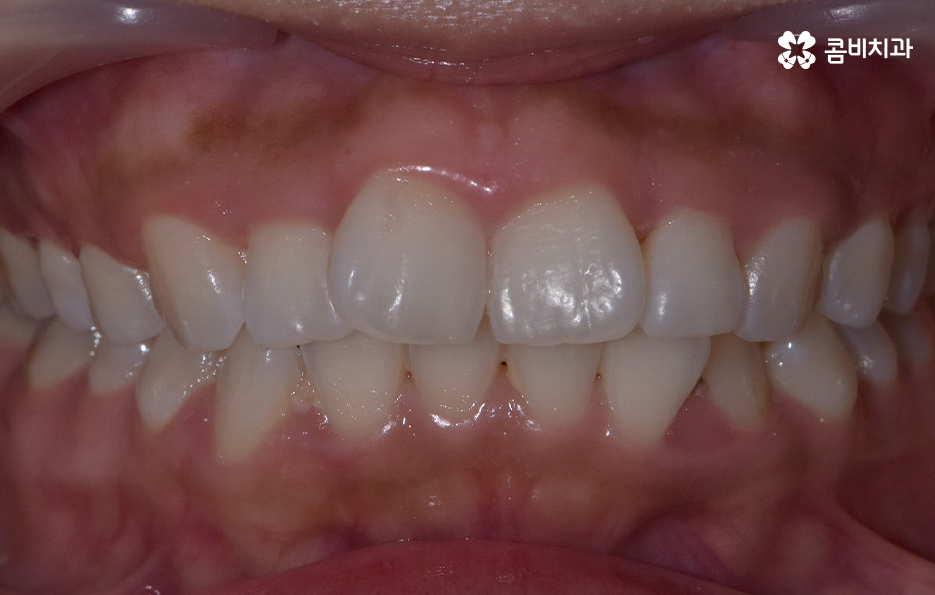

앞니가 살짝 틀어져 있다는 사실은 이미 전부터 알고 있었어요 하지만 그때는 이 정도면 괜찮겠지, 사람마다 치열이 완벽하게 곧을 필요는 없겠지 하며 대수롭지 않게 넘겼어요 거울을 볼 때 조금만 입술을 다물어도 크게 티가 나지 않는 것 같아 굳이 치료를 생각하지 않고 지냈어요

그런데 어느 순간부터 누군가와 마주보고 웃을 때, 사진을 찍을 때, 말을 할 때조차 그 작은 틀어짐이 내 시선의 중심에 자꾸 걸리기 시작했어요

내가 생각하는 나의 이미지와 거울 속 모습 사이의 미묘한 차이가 점점 더 크게 느껴졌어요 처음엔 가벼운 걸림이었지만 시간이 갈수록 그것이 확실한 고민으로 바뀌어 갔어요 특히 사진을 찍을 때마다 그 불편함이 더 선명하게 다가왔어요

친구들과 함께 찍은 평범한 사진에서도 내 앞니가 살짝 돌아가 있는 모습이 먼저 눈에 들어왔어요 남들이 보기엔 별게 아닐 수도 있지만 정작 본인에게는 그 작은 비대칭이 너무 크게 느껴지는 순간들이 있었어요 이 불편함이 점점 일상 속 행동까지 바꾸기 시작하면서 드디어 교정을 고민하게 되었어요

이처럼 교정을 결심하게 되는 계기는 다양한데 그 중에서도 앞니 틀어짐 교정 방법은 그 정도에 따라서 치료 방법이 다양하다 보니 어떤 분들은 비교적 간단한 치료가 가능하고 어떤 분들은 전체교정을 해야 하다보니 치료 방법의 갭차이를 크게 느끼시는 분들도 많이 있는데요

특히 앞니는 사람의 첫인상과 발음을 결정짓는 중요한 치아라 조금만 틀어져도 눈에 잘 띄고, 스스로도 불편함을 크게 느끼게 되는데 앞니 틀어짐 교정 방법의 차이는 기본적으로는 치열의 복잡성이나 치아가 이동해야 하는 정도, 교합 등의 차이에서 나타나기 때문에 치료 방법을 구체적으로 이해하기 위해서는 앞니가 틀어지는 원인과 치아교정의 원리를 알아가는 것이 도움이 될 거예요

앞니 틀어짐 교정 방법 경미한 수준일 때는 부분 교정 방식은 치료 기간이나 방법 면에서 비교적 간단한 치료가 가능한데 앞니 6개 정도에만 브라켓을 부착해 미세한 틀어짐을 바로잡는 방식으로 치아가 크게 회전하지 않았거나 공간이 약간 부족한 정도라면 효과적이며 기간도 보통 3~6개월로 짧은 편으로 이 방식은 앞니 배열을 빠르게 정리하면서도 자연스러운 라인을 만들 수 있어요.

다만 부분교정 방식은 교합 문제까지 해결하기는 어렵기 때문에 교합이 안정적인 경우에 적합하기에 경미한 케이스에 적합하다고 한정 지을 수 있었어요

두 번째 방법은 투명 교정(인비절라인 등)으로 앞니만 틀어진 경우 투명 교정은 효율적이고 눈에 띄지 않아 일상생활도 편한데 경미한 앞니 틀어짐은 투명 교정이 자연스럽고 부담이 적은 방식으로 투명 교정으로 앞니를 조금씩 배열을 맞추는데, 특히 벌어짐이나 약한 회전 교정에 효과가 좋으며 이러한 방식은 투명교정 장치의 착용 시간이 중요하기 때문에 하루 20시간 정도 착용해야 원하는 속도, 결과가 나온다는 특징이 있어요.